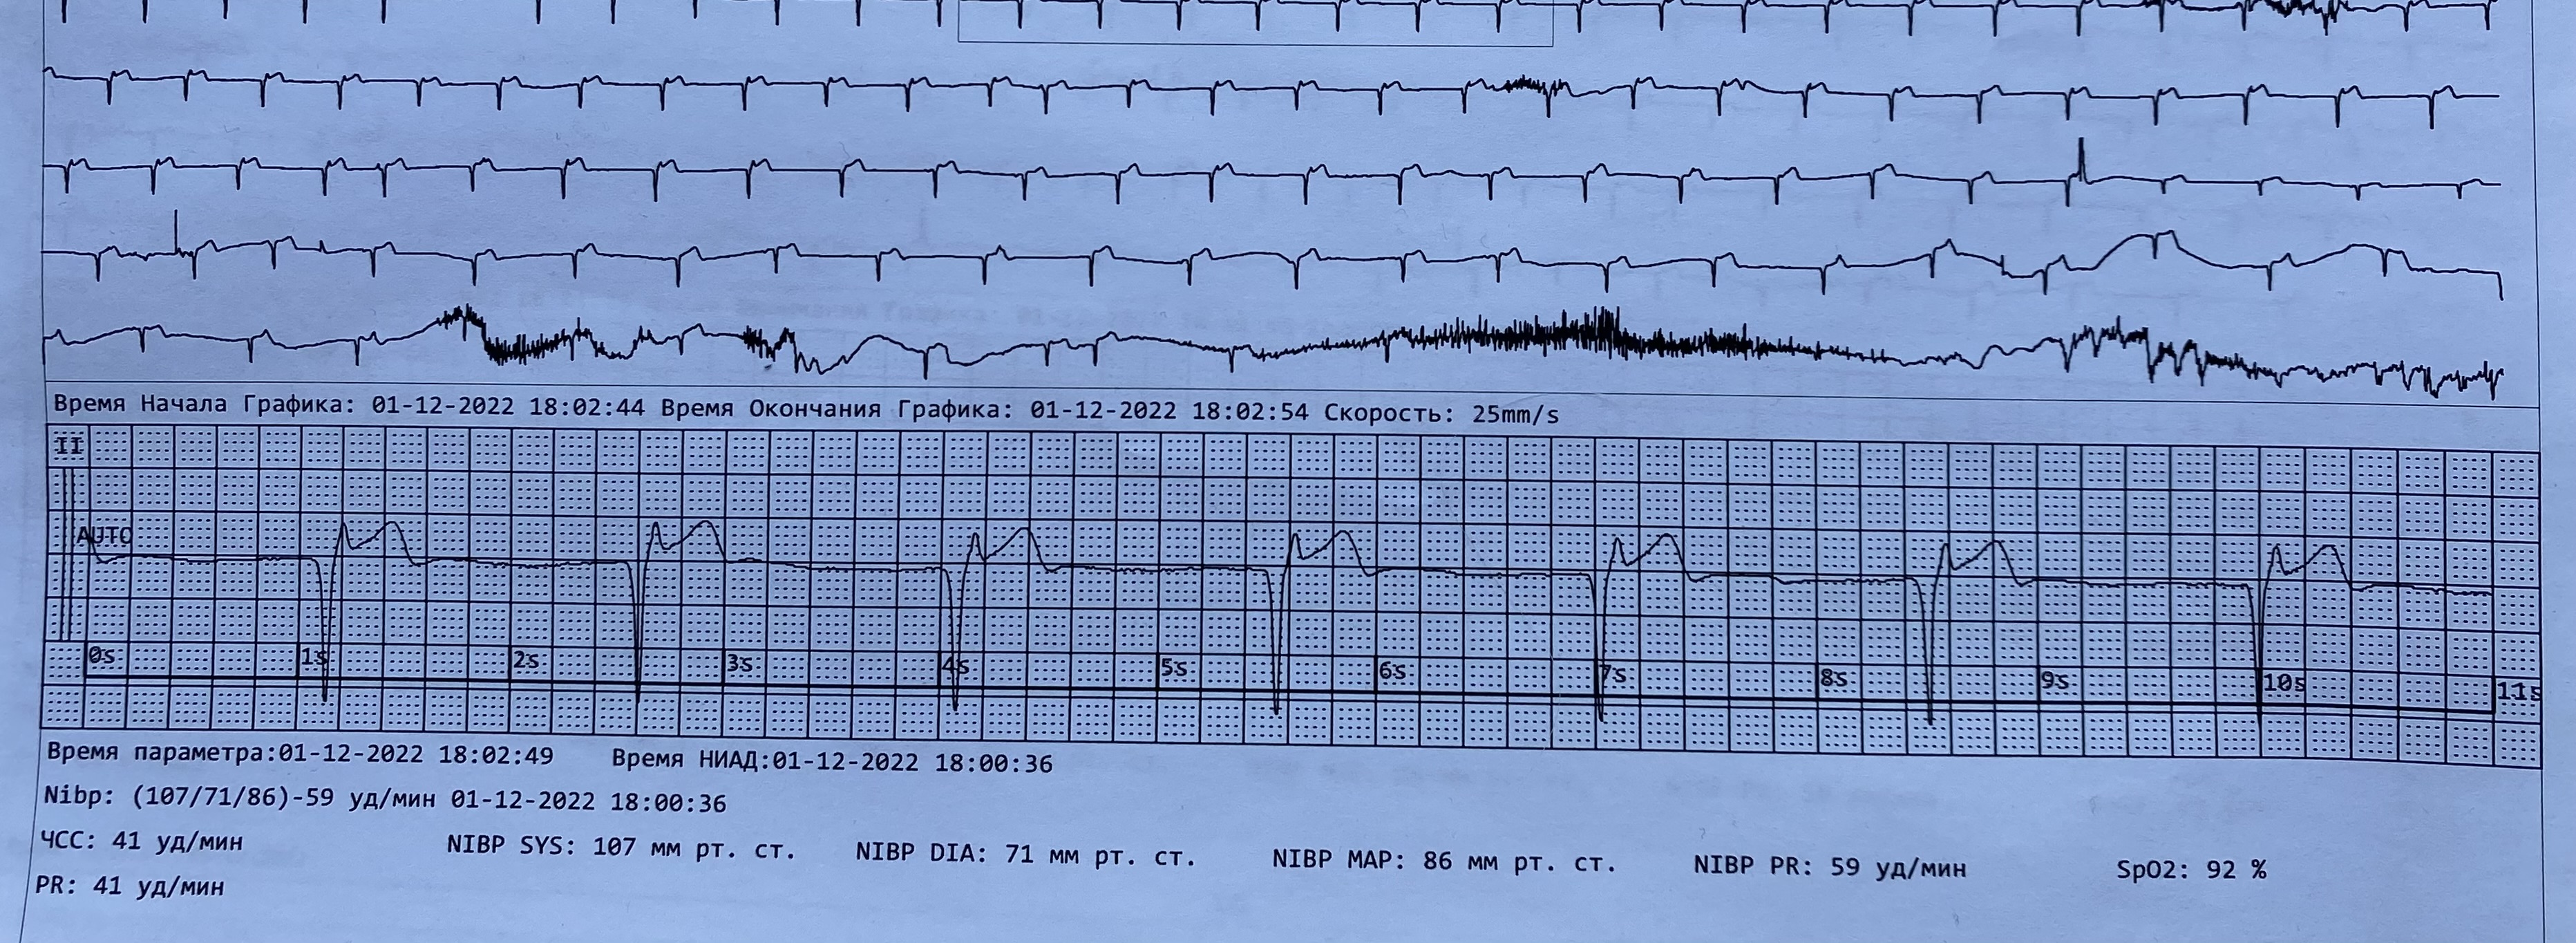

Не очень классически, но это МВР

Обсуждалось в Госпитале Ослабленных Сердец

4.JPG

4.JPG [ 1.63 MiB | Просмотров: 24383 ]